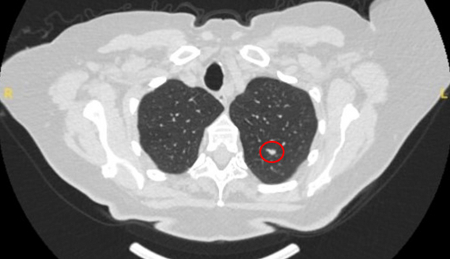

Solid nodules: volume doubling time of >600 days does not require follow-up, while a volume doubling time of <400 days, or clear growth defined as an increase in volume of 25% or more, suggests diagnostic investigations are required.[Figure caption and citation for the preceding image starts]: Computed tomography (CT) showing a right upper lobe spiculated solitary nodule within emphysema, in a current smoker with previous asbestos exposure. Note the visible pleural plaque on the left side. Resection histology revealed adenocarcinoma of the lungFrom the collection of Dr George Tsaknis, MD, PhD, FRCP(London), MRQA, MAcadMEd, PGCert; used with permission [Citation ends].